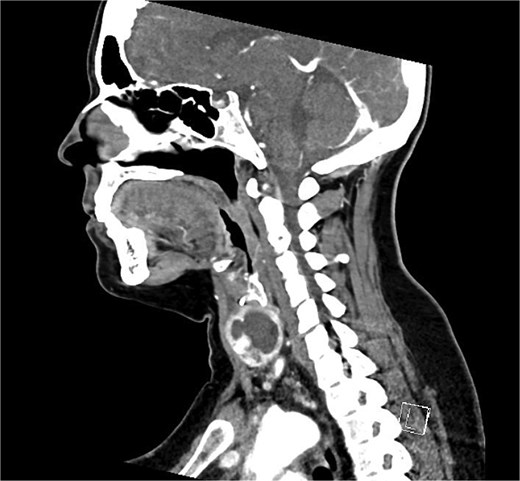

Bloods demonstrated elevated inflammatory markers with a neutrophil count of 7.53 and C-reactive protein of 137. Her biochemistry panel including thyroid function tests were within normal limits. An ultrasound (USS) was performed which showed a cystic/solid nodule in the left thyroid gland that measured 30 × 42 × 22 mm with an estimated volume of 14 ml (Fig. 1). A computed tomography (CT) scan was conducted to ensure no airway compression, it demonstrated the abscess to measure 32 × 26 × 32 mm (Figs 2 and 3). There was no tracheal compression but there was mild inflammatory stranding and hyperenhancement of the nodule consistent with infection.

Sagittal portal venous phase CT of the neck demonstrating the cystic lesion in the left thyroid gland.